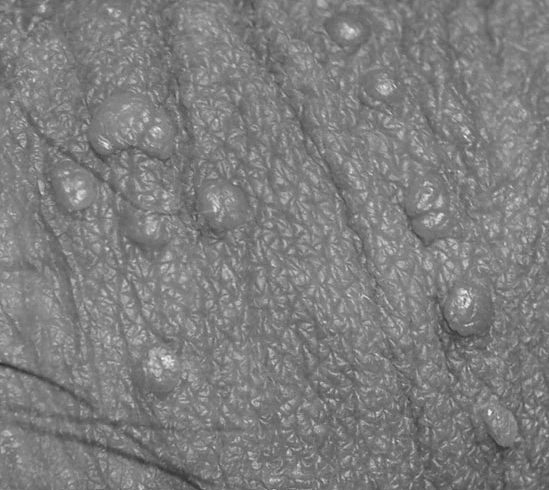

곤지름 감염 후, 방치하면 벌어지는 일

곤지름 감염 후, 방치하면 벌어지는 일 재발을 막는 한방 면역치료가 필요한 이유 알고 나면 더 무서운 곤...